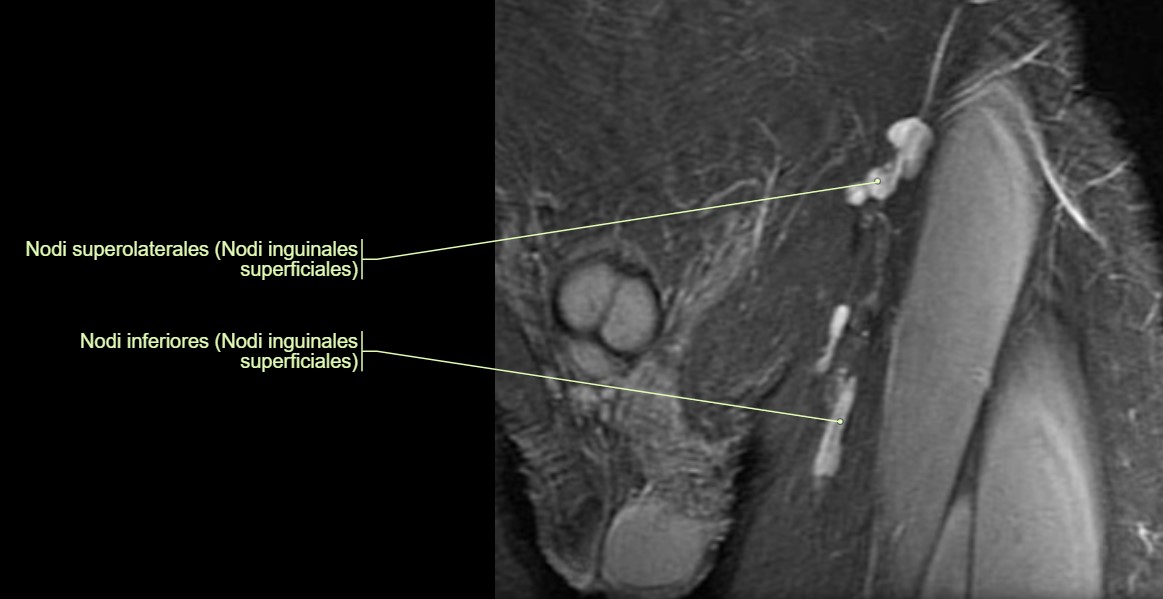

Lymphknoten in der MRT

Lymphknoten sind auf einer MRT (Magnetresonanztomographie) sichtbar, weil sie als Teil des Lymphsystems spezifische Gewebeeigenschaften besitzen, die sich von umliegenden Strukturen unterscheiden. Die MRT nutzt ein starkes Magnetfeld und Radiowellen, um detaillierte Bilder des Körpergewebes zu erzeugen. Dabei macht sich die MRT vor allem Unterschiede in der Wasserstoffkonzentration und den physikalischen Eigenschaften des Gewebes zunutze.

Lymphknoten bestehen aus lymphatischem Gewebe, das eine höhere Dichte an Zellen und Flüssigkeit aufweist als umliegende Strukturen wie Fettgewebe. Diese Unterschiede in der Gewebszusammensetzung führen dazu, dass Lymphknoten je nach verwendeter MRT-Sequenz anders erscheinen als das umliegende Gewebe. Es gibt verschiedene Sequenzen in der MRT, die unterschiedliche Gewebetypen besser hervorheben können.

Zusätzlich können veränderte oder vergrößerte Lymphknoten, die auf Infektionen, Entzündungen oder Tumore hinweisen, noch deutlicher sichtbar sein. In solchen Fällen verändern sich die Eigenschaften der Lymphknoten und sie heben sich noch stärker von gesunden Strukturen ab, was sie auf den MRT-Bildern leichter erkennbar macht.

MRT-Bilder mit Anatomie von Lymphknoten im Becken, Lymphknoten im Halsbereich, sowie einem Lymphknoten im Bereich des Schlüsselbeins: